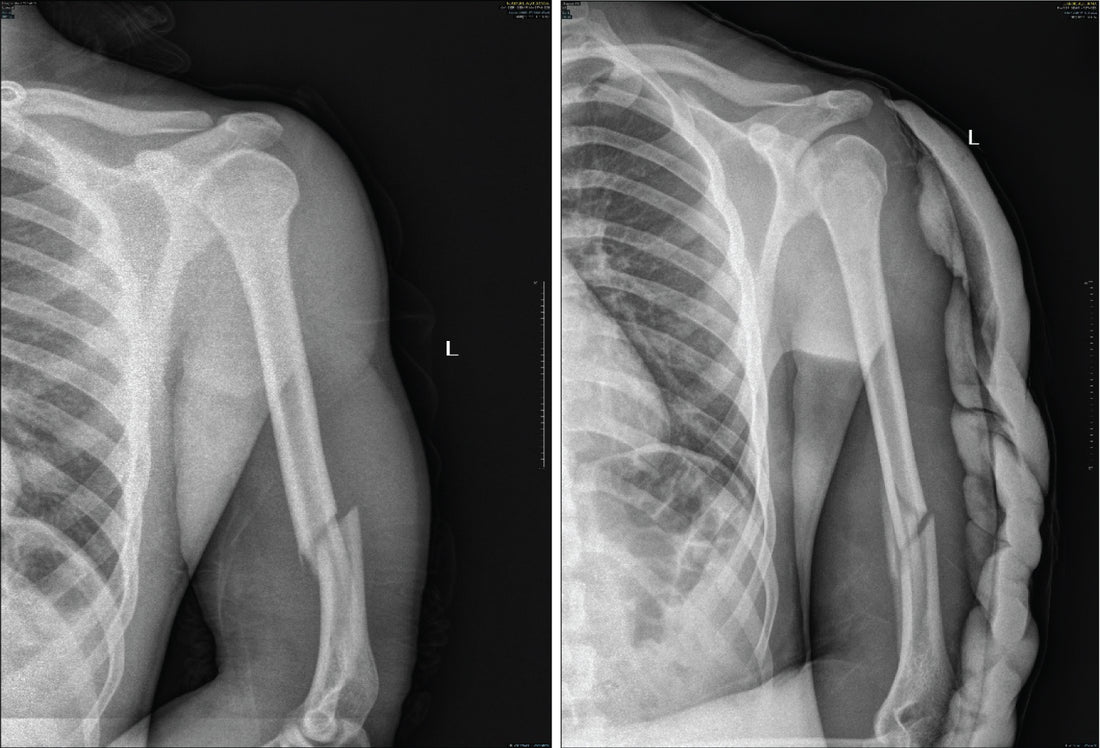

• Don’t Allow a Hyperextended Elbow: One of the most common ways arm breaks happen is from hyperextension of the elbow. Be mindful not to allow your arm to extend too far backward during a match. Always maintain a natural, safe arm position.